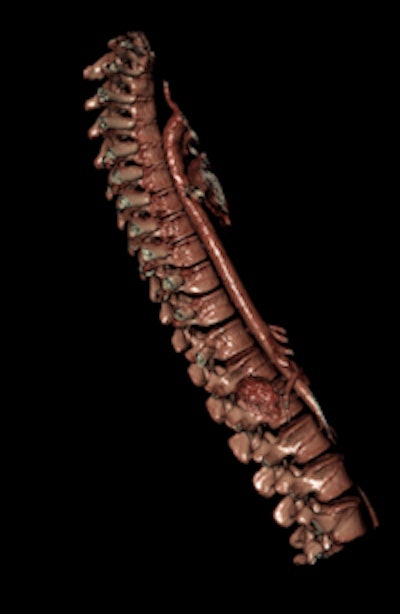

Visualization of the vertebral column, which is not straightforward in a classical autopsy because dissection of the spine is time-consuming and involves the sawing of the spinous process of vertebral bodies.

The scanning module, iDASS (Digital Autopsy Software Systems), lies at the heart of the process, enabling pathologists to visualize and analyze a complete 3D image of a body in near real-time. In expected and nonsuspicious deaths in the elderly, for example, the system will allow proper documentation of a death, even if imaging is not required, while at the other end of the scale, the system can cater for a full criminal investigation forensic autopsy, complete with 3D panoramic views of the crime scene, according to Chandran.